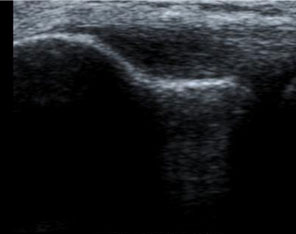

eco-aumento vascolarizzazione

• Ecografia: può mostrare cambiamenti strutturali che interessano i tendini (come ad esempio ispessimento, assottigliamento, aree degenerative, lesioni e/o calcificazioni, grado di vascolarizzazione dei tessuti).